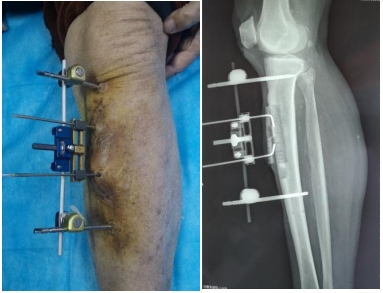

患者男性,86岁,糖尿病足坏疽,动脉硬化闭塞症,心脏支架术后,术前静息痛、冰凉感、麻木症状明显,每天口服6片氨酚双氢可待因片不能缓解疼痛。于2020年10月10日在我院行胫骨横向骨搬移手术。